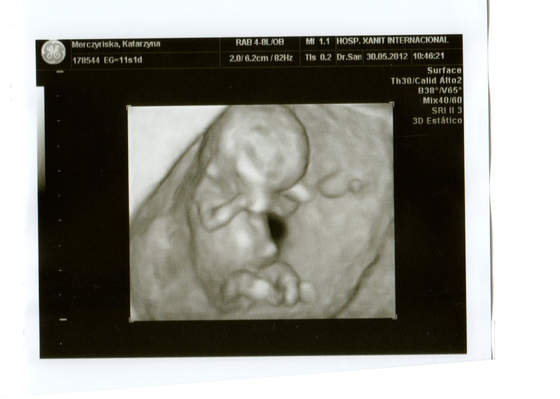

Zrobil mi juz USG genetyczne przez powloki brzuszne i wszystko pieknie widzialam. Z dzidzia wszystko w porzadku. Widzialam juz glowe, raczki, nozki i oczywiscie slyszlam serduszko. Straszie ruchliwy byl bo fikal nogami ze hej. Cudowny widok !!!

Moja dzidzia ma juz 4,5 cm. I wyglada na to ze wszystko jest w najlepszym porzadku.

Wrzucam zdjecia...